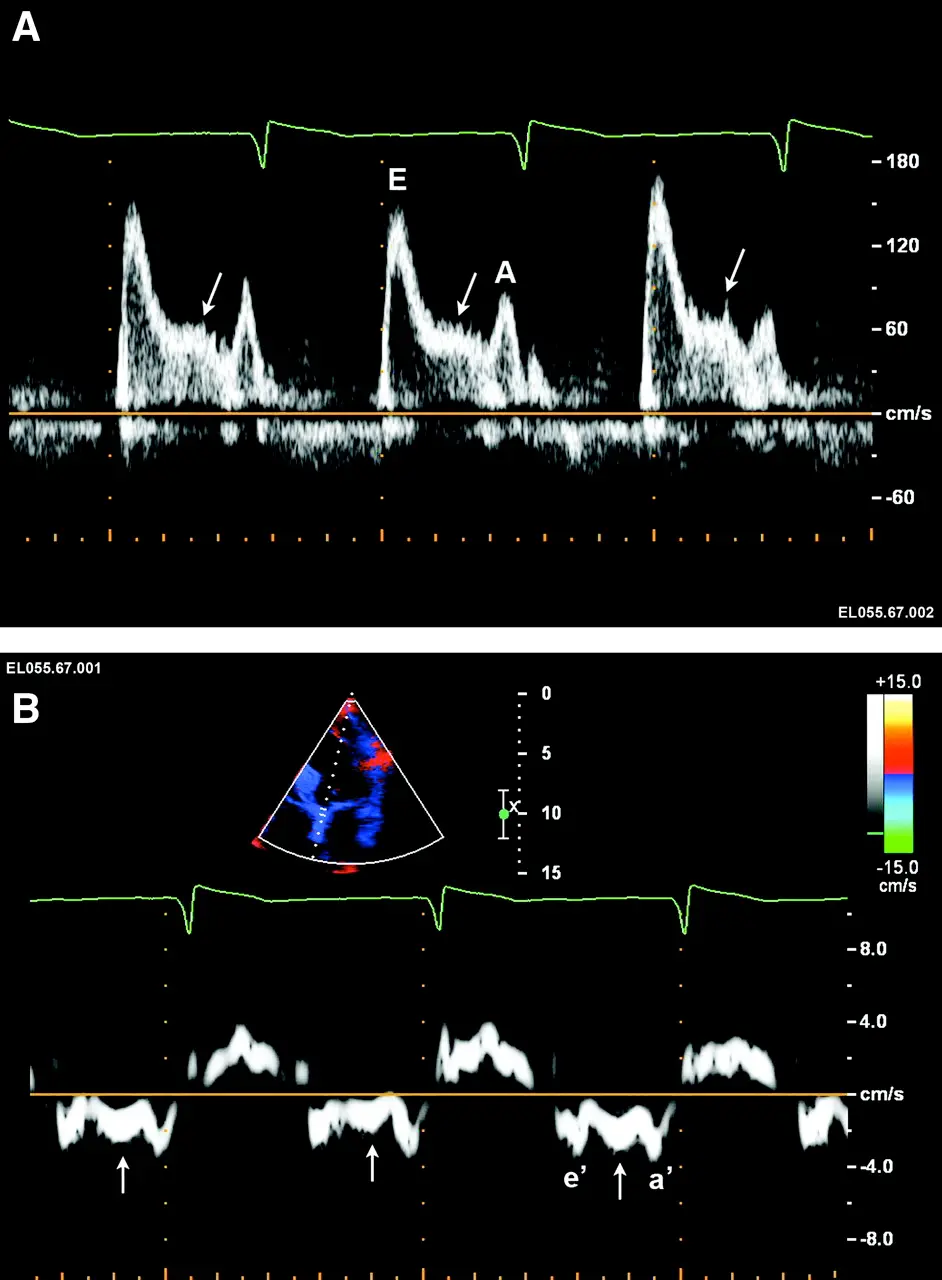

Mitral inflow velocity: Peak E-wave velocity (cm/s) is the peak early diastolic modal velocity after ECG T wave

Mitral inflow velocity: Peak A-wave velocity (cm/s): peak late diastolic modal velocity after ECG P wave

Mitral annular velocity: e’ velocity (cm/s): peak early diastolic modal velocity after ECG T-wave

Mitral annular velocity: a’ velocity (cm/s): peak late diastolic modal velocity after ECG P-wave

Figure source: 3. The arrow (→) corresponds to the L wave, which is due to elevated filling pressure and delayed myocardial relaxation

Mitral inflow pattern in a ~30 yo patient with severe LVH who initially presented with HTN emergency.

If you just base it off the patient having medial e’ >6, lateral e’ >7, or average >6.5, then you may conclude that she has normal diastolic function. However, I’d argue that this would be incorrect. The patient is a ~30 yo with severe LVH. Bearing in mind her young age, you should expect her e’ velocities to be much higher if she truly had normal diastology. With her very high E/A ratio, she has Grade 3 DD.